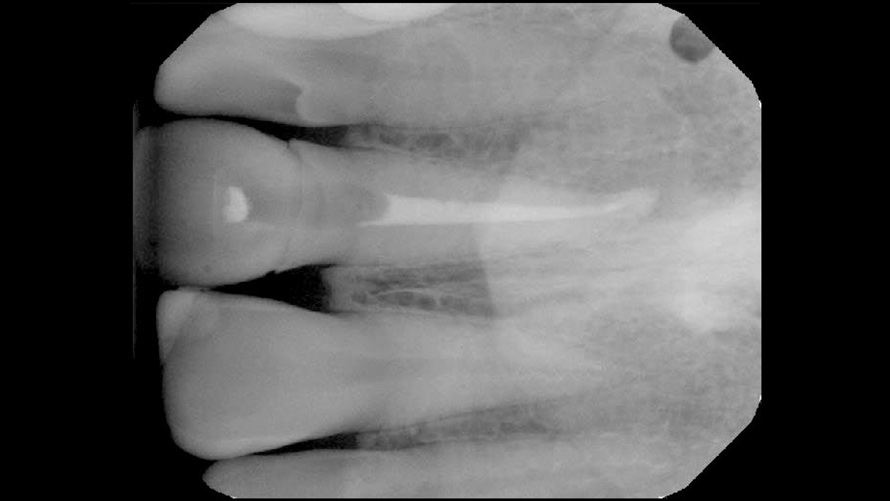

In the first case, the patient reported a history that included childhood dental trauma without swelling or discomfort. The intraoral examination indicated that the existing all-ceramic restoration on tooth No. 8 possessed an inappropriate morphology, surface topography, and shade. Radiographically, tooth No. 8 exhibited a large underlying resin core with significant porosity and periapical radiolucency (Figure 3). The diagnosis for tooth No. 8 was pulp necrosis with asymptomatic apical periodontitis.

(3.) Case 1: Preoperative radiograph of the maxillary right central incisor, demonstrating periapical radiolucency and porous core buildup.

Figure 3